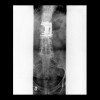

Columna cervical